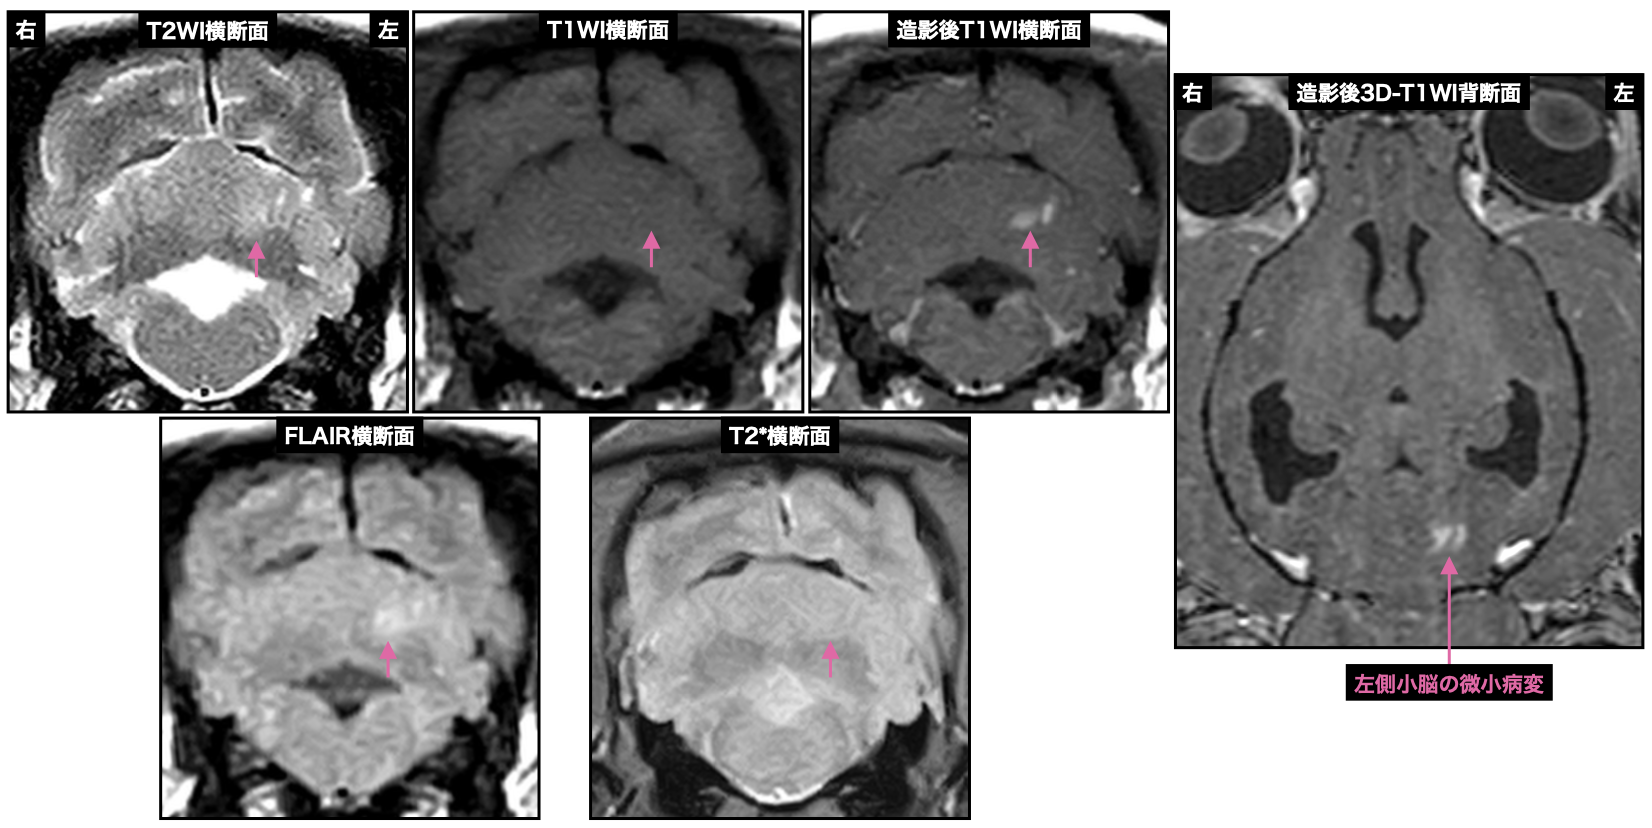

過去に起こしたと思われる多発性脳出血の所見が偶発的に認められた14歳のチワワ、これに関連した症状はなかった